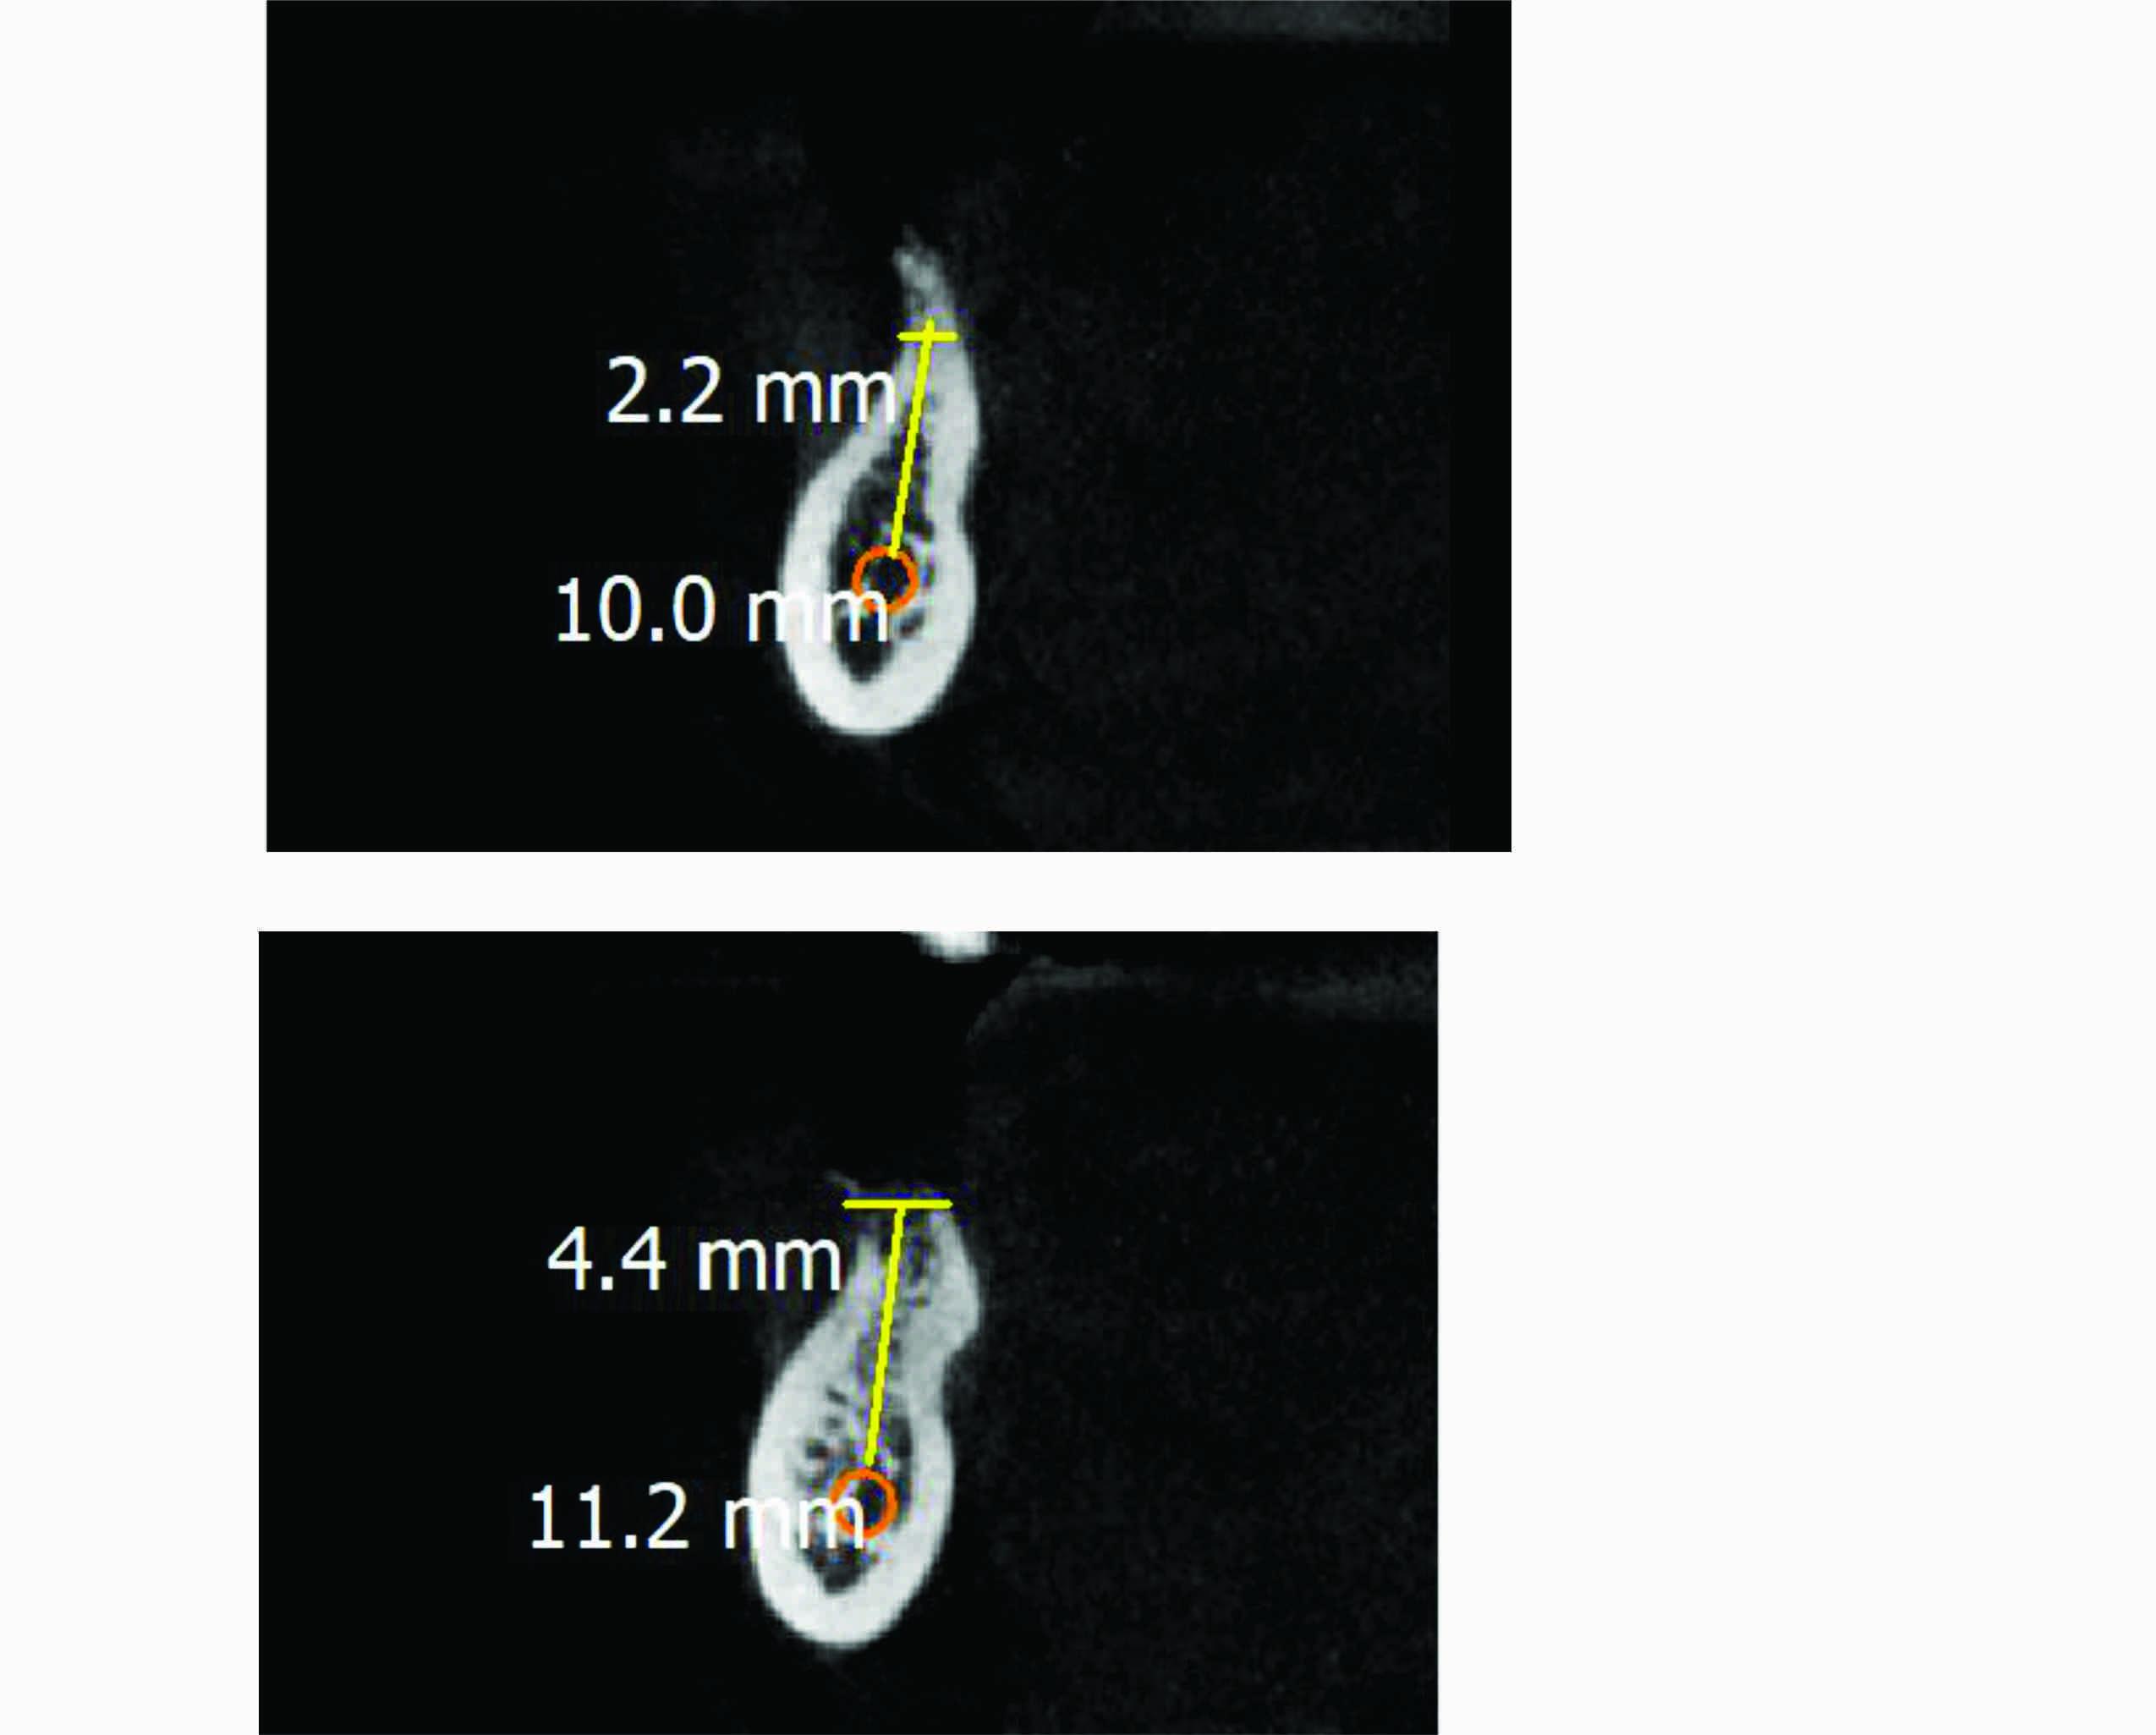

The CBCT report says that in LR 1st molar area the height from crest of alveolar bone to I.A.N is 10 mm and width is 2.2 mm .

In 2nd molar area the height from crest of bone to I.A.N is 11.2 mm and width is 4.4 mm.